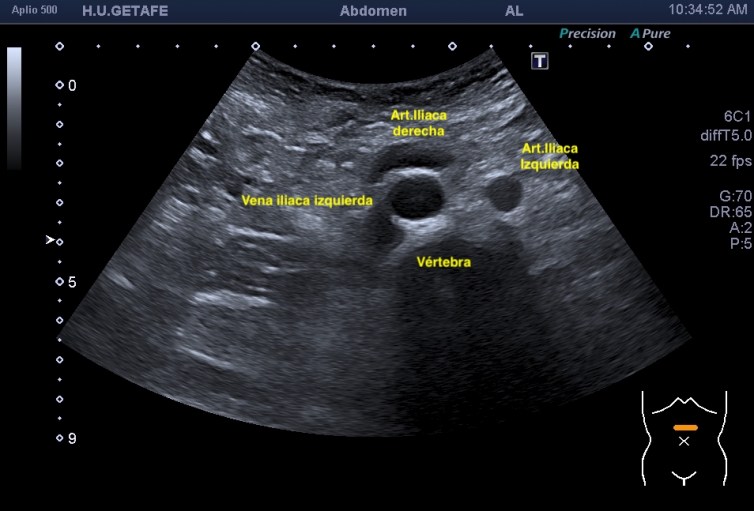

Lo que ves en estas imágenes que te voy a poner aquí son los hallazgos ecográficosque he podido visualizar hoy. Los voy a complementar con la correlación con las imágenes de TAC. En este caso específico con la eco solo se pudo corroborar los hallazgos del escáner, que a nivel anatómico arroja un mejor desarrollo de la anatomía regional implicada en el proceso.

En el corte axial de las imágenes 3 y 4 puedes ver la anatomía radiológica implicada. La relación es perfecta, y completamente explicativa de la situación resulta mediante el tratamiento quirúrgico. En ella la Arteria iliaca derecha para justo por encima de la Vena iliaca Izquierda con la capacidad de poder comprimirla.